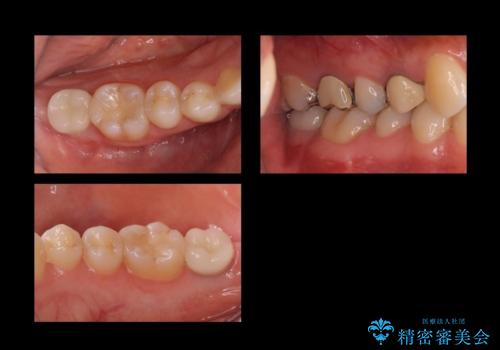

合計3本の奥歯を抜歯したところに、インプラント治療を行っています。

また、左上奥歯の根の治療および右下の虫歯治療も併せて行っています。

- 199.1万円 内訳:右下7、左下67(ストローマンインプラント 22万円×3本 チタンカスタムアバットメント 11万円×3本 ジルコニアクラウン11万円×3本 インプラント用仮歯 2.2万円×3本 骨増生 5.5万円×2ヶ所) 左上67(精密根管再治療 14.3万円×1本、仮歯1.1万円x2本、ジルコニアクラウン11万円×2本)右下6(セラミックインレー 7.7万円)プレミアムナイトガード 3.3万円費用は治療当時の料金となります